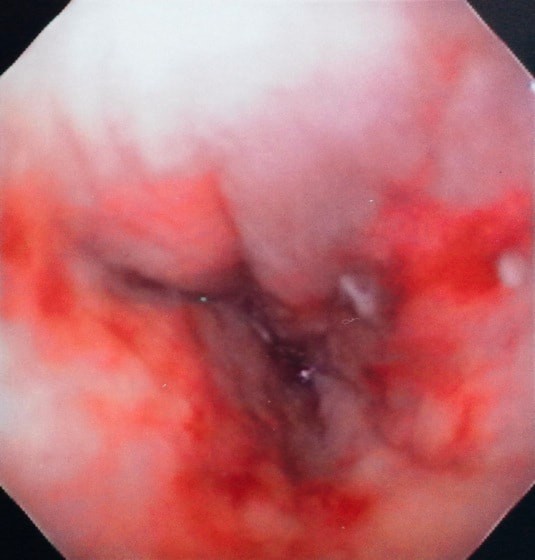

経過:超音波検査にて直腸壁の肥厚(5㎜)が認められた。また、直腸検査で直腸全周に結節状病変を触知し、出血も確認された。消炎剤、抗生剤、整腸剤による治療への反応が長期的に悪いため、生検も含めた内視鏡検査を実施した。

内視鏡検査:肛門付近の直腸全周に、炎症および出血を伴う結節状病変を多数認めた。

病理検査:直腸の病変は、良性の非腫瘍性病変の一つである“炎症性ポリープ”と診断された。

診断後経過:炎症性ポリープは多発する傾向や腫瘍に転化する可能性があるため、消炎剤、抗生剤、整腸剤による内科療法を継続しながら、現在プルスルー法による外科的摘出術を検討中。